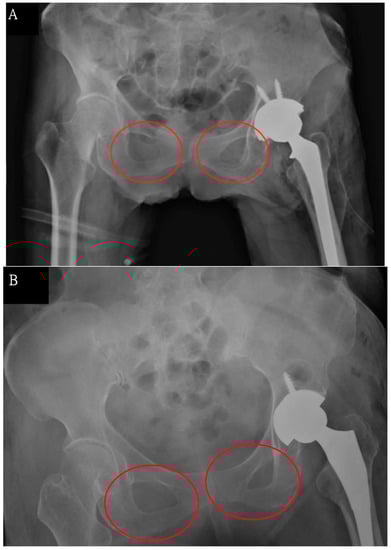

2.3. Anatomical Landmarks on Radiographic Images

Yeh, K.-L.; Wu, T.-Y.; Fuh, C.-S.; Chen, C.-S.; Hou, S.-M.; Chiang, C.-H.; Liaw, C.-K. Degree of Pelvic Rotation in the Coronal Plane on Postoperative Radiographs Obtained after Total Hip Arthroplasty. J. Clin. Med. 2022, 11, 6353. https://doi.org/10.3390/jcm11216353